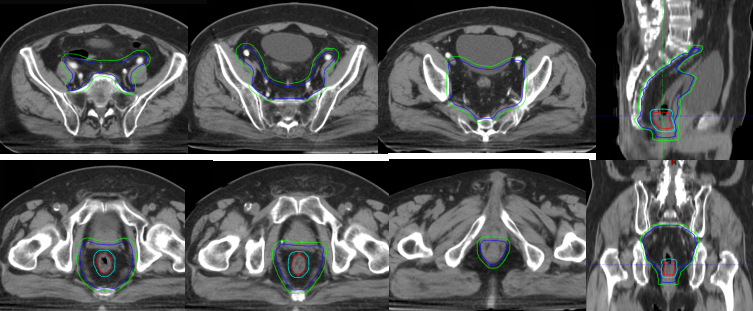

原发灶放疗靶区

原发灶治疗后